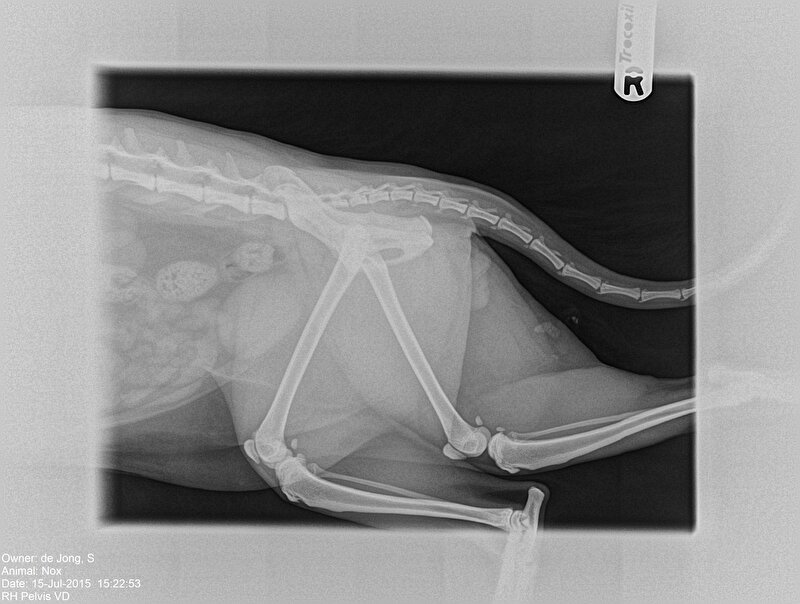

L3 tot D9 is vastgezet.

Jolynne schreef:Mijn eigen rug

Enkele maanden voor mijn operatie, net voor operatie was deze veel erger (o.a. 60% longcapaciteit)

de schroef en het plaatje zijn er uit en vervangen voor een ijzerdraad die nu alles op z’n plek houdt hahah